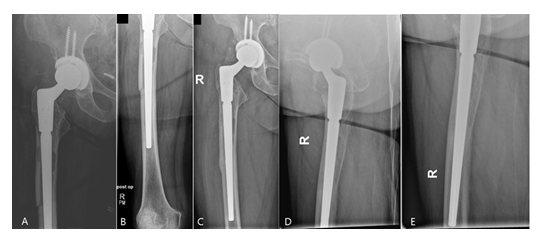

Intraoperatively, the beads could be completely removed through an endofemoral approach without having any difficulties. Based on the bone quality, presence of any osseous defects and occurrence of fractures, a cementless modular straight stem (Restoration® , Fa. Stryker, Duisburg, Germany) was used in 14 cases and a cemented proximal femur replacement stem (GMRS®, Fa. Stryker, Duisburg, Germany) in four cases, respectively. In the latter cases, the bone defects and the non-intact femoral isthmus would not have provided for a sufficient cementless fixation, therefore cemented implants were solely chosen. In all cases, Palacos R+G® (Fa. Heraeus Medical, Bad Homburg, Germany) was used. The abductor muscles were fixated onto the prosthesis through the fixation holes with non-absorbable sutures (Ethibond Excel 2-0, Fa. Ethicon). For the acetabulum, a press-fit cup (Tritanium®, Fa. Stryker, Duisburg, Germany) and an antiprotrusio cage combined with a cemented cup (Burch-Schneider cage, Fa. ZimmerBiomet, Freiburg i. Br., Germany) were implanted in eight cases, respectively, whereas a bipolar head (UHR®, Fa. Stryker, Duisburg, Germany) and a cemented constrained liner (Trident®, Fa. Stryker, Duisburg, Germany) were used in one case, respectively. Suction drains were routinely placed in all cases. The mean surgery time of the second stage was 162 [84-319] minutes. Depending on the osteotomy length, the total length of the Restoration® stems used varied between 225 and 295mm (9x 155mm, 5x 195mm with various length of cone bodies) (Figure 9). Postoperatively, all patients were allowed to put full weight-bearing onto the operated leg.

At a mean follow-up of 43 [24-85] months 16/17 (94%) of the cases that underwent prosthesis reimplantation were free of any local or systemic infection signs. There was no case of a stem subsidence. All osteotomies showed a complete osseous consolidation after three to six months (Figure 9).